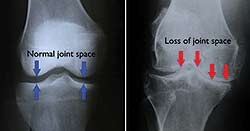

The answer to all of these mysteries lies in the name "arthritis" itself: "-itis" indicates that this is an inflammatory condition, not merely a consequence of overworking a joint, even if repetitive activities do in fact contribute to the problem.

In the decades since I graduated from medical school, research has revealed that arthritic joints have both low-grade infections and insulin resistance. Both of these are highly inflammatory. Historically, doctors have treated inflammation with anti-inflammatory medications, such as Ibuprofen, Naprosyn, Celebrex, and the like. But these and other drugs only relieve symptoms for hours at a time. Once the pain gets bad enough, doctors inject more potent anti-inflammatories called corticosteroids directly into affected joints, yielding seemingly miraculous results, at least for a few months. Published studies have been unable to prove any long-term benefit.

While both of these approaches provide pain relief, neither has any effect on the underlying causes of arthritis or on the course of the disease. More concerning, all anti-inflammatory drugs increase your risk of heart attack, stroke, bleeding ulcers, kidney damage, high blood pressure, and more. One review reported that 30% of all drug-event-related hospitalizations are due to NSAIDs. And steroid injections are not without risk, either. If you have diabetes, one of these injections can raise your blood sugar for a period of months. Moreover, whereas we used to think there was no limit to the number of injections a joint could handle, recent studies have demonstrated that steroids actually increase damage to cartilage, leading to sooner joint replacement.